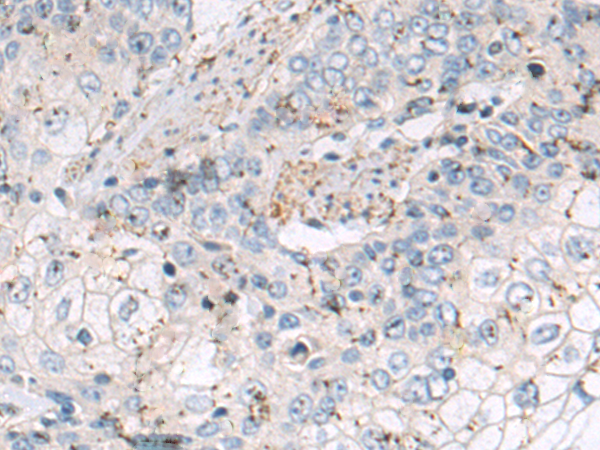

分类: 科研抗体货号: P10605别名: CMT2Q; AMOXAD应用: IHC反应种属: Human, Rat